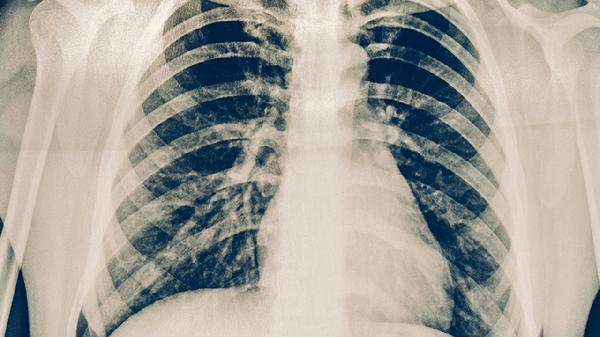

中醫(yī)治療肺結核需辨證施治,不同階段采用相應方藥。治療期間應保持情緒穩(wěn)定,避免勞累,居住環(huán)境需通風但避風寒。飲食宜清淡營養(yǎng),忌煙酒及辛辣刺激。需定期復查胸部影像學,若出現(xiàn)大咯血、呼吸困難等急癥應立即就醫(yī)。中西醫(yī)結合治療可提高療效,抗結核西藥不可擅自停用。